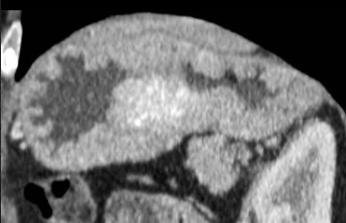

Tumeur endocrine

infiltrant de estoma . Image isodense avec des

nodules hyperdenses de hypervascularises . |

Image TDM d'une tumeur

endocrine de l' estomac |